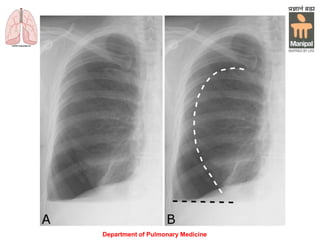

• Chest X-ray shows the sharply defined

translucency (no lung markings) between

INVESTIGATION • Chest X-rayshows the sharply defined edge of the deflated lung with complete translucency (no lung markings) between this and the chest wall • CT Thorax if in doubt • Investigations aimed at finding the cause (e.g. Pulmonary TB, COPD) Department of Pulmonary Medicine